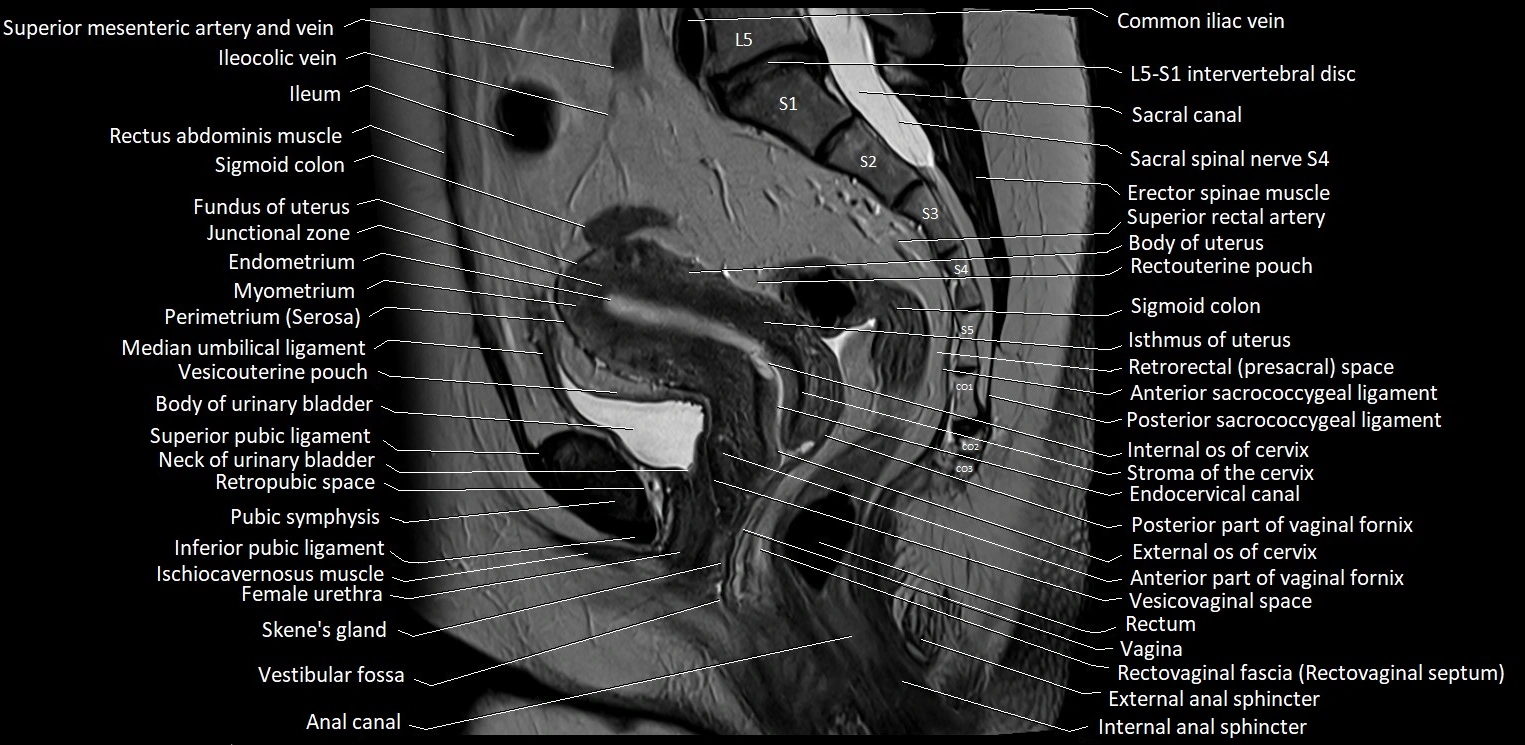

- Body of urinary bladder

- Body of uterus

- Coccyx

- Common iliac vein

- Endocervical canal

- Endometrium of uterus

- Fundus of uterus

- Ileum

- Internal os of the cervix

- Isthmus of uterus

- Junctional zone of uterus

- L5–S1 Intervertebral disc

- Median umbilical ligament

- Myometrium of uterus

- Perimetrium of uterus

- Posterior fornix of cervix

- Pubic symphysis

- Rectouterine pouch (pouch of Douglas)

- Rectovaginal septum (rectovaginal fascia)

- Rectum

- Retropubic space

- Sacral canal

- Sigmoid colon

- Skene’s gland (paraurethral glands)

- Superior rectal artery

- Uterosacral ligament

- Vagina

- Vesicouterine pouch

- Vestibular fossa